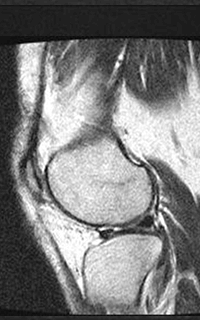

As some say, seeing is believing. Check out the images below which compares a low strength, open machine to a 1.5T, high-field machine. The difference in quality from one scan to another speaks for itself.

MRI of the Knee: High-field 1.5T MRI on the left; low-field, open on the right.